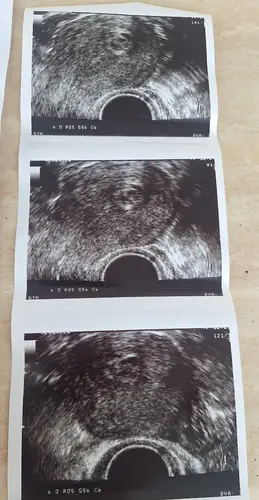

Mijn echo is gister heel anders gegaan dan verwacht en ben daar best van in de war. Ik ging erheen met het idee dat ik zou horen dat alles ‘schoon’ was, maar ze zag dat het vruchtzakje was gegroeid en dat er toch iets in zat. Wel deels losgelaten, dus daar komt het bloedverlies vandaan.

Het voelt gek om ergens zeker te zijn dat het niet goed zit, maar nu toch 1% hoop te hebben.. Ik heb een foto van een echo, maar werkelijk geen idee wat er op te zien is.. Gynaecoloog had ook een 24 uurs dienst en 3 bevallingen gedaan dus wilde geen extra vragen stellen..

Ik heb toen mijn bloedverlies op zaterdag (11 oktober) begon ook een echo gehad, daarop was ook nog een in tact vruchtzakje te zien, maar deze was echt "mooi" rond. Op zondag (12 oktober) kreeg ik weer een echo, en zag ik ook nog een vruchtzakje... maar deze was toen helemaal in elkaar gezakt en een beetje opgedeeld zegmaar, en het zag er een beetje uit als de echo die jij stuurt... Daaruit concludeerde de verloskundige dat het mis ging, omdat het dus echt niet meer rond was als de dag ervoor....